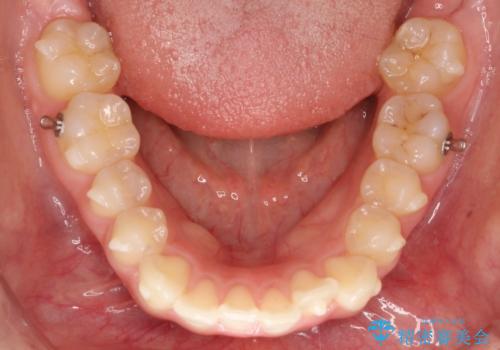

下顎前歯の叢生を短期間で改善

- 患者様は、下顎前歯のガタガタ(叢生)の改善を希望して来院されました。診断の結果、非抜歯で治療可能であると判断し、透明で目立たないインビザラインを使用する矯正治療計画を立案しました。短期間での治療を希望されていたため、IPR(歯間削合)を併用してスペースを確保しながら、効率的に歯を並べることを目指しました。

治療では、インビザラインを用いて計画的に歯を移動させ、短期間での歯列改善を実現しました。IPRを行うことで、抜歯をせずに必要なスペースを確保し、歯列全体を整えました。治療中は、装置の適切な装着時間を守ることが重要であり、患者様にも継続的な協力をお願いしました。また、歯肉や歯根への負担を最小限に抑えるため、歯の移動を慎重に管理しました。結果として、短期間で下顎前歯の叢生を改善し、自然な見た目と機能性を兼ね備えた歯列を実現できました。